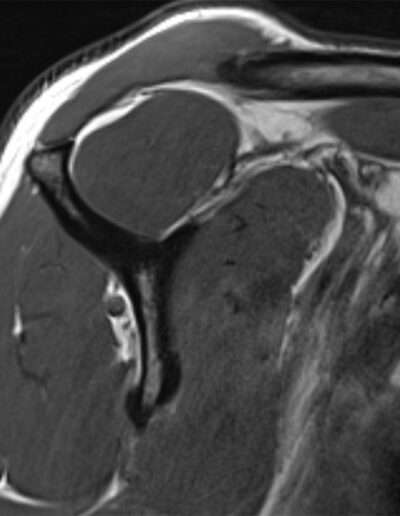

F02: SLAP VIII + MASSIVE COMPRESSIVE CYST ON SSN

Shoulder Right

Patient 39 y/o, Female, Right-hand dominant

Profession/Sport Childcare assistant / Pole dance

History

• 10/2024: Shoulder pain without trauma

• 2025: Progressive loss of strength without pain